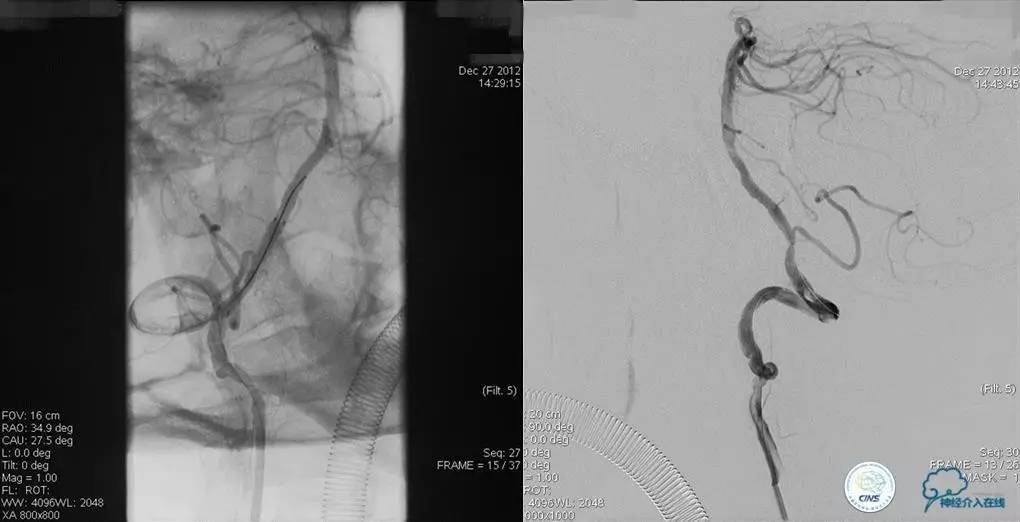

术前DSA

▼2013-12-13

▼2013-12-27

术后仍残余部分狭窄,但头晕明显缓解。

术后3个月复查时予行支架内球囊扩张,狭窄改善。